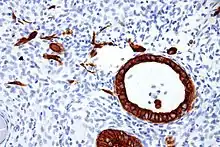

Cytokeratins are keratin proteins found in the intracytoplasmic cytoskeleton of epithelial tissue. They are an important component of intermediate filaments, which help cells resist mechanical stress.[1] Expression of these cytokeratins within epithelial cells is largely specific to particular organs or tissues. Thus they are used clinically to identify the cell of origin of various human tumors.

Expression of these cytokeratins is largely organ or tissue specific. The subsets of cytokeratins which an epithelial cell expresses depends mainly on the type of epithelium, the moment in the course of terminal differentiation and the stage of development. Thus a specific cytokeratin expression profile allows the identification of epithelial cells. Furthermore, this applies also to the malignant counterparts of the epithelia, (carcinomas), as the cytokeratin profile is generally retained. Thus the study of cytokeratin expression by immunohistochemistry techniques is a tool of immense value widely used for tumor diagnosis and characterization in surgical pathology.[5]